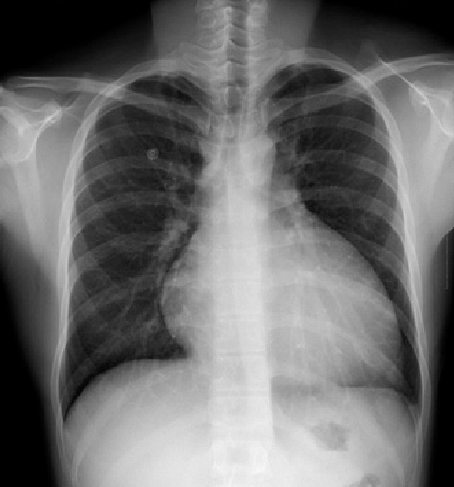

НУ Интеллектуалды жүйелер және жасанды интеллект институтының ғалымдары кеуде қуысының рентгенографиясын диагностикалауға арналған ақысыз жүйені ұсынды. Енді кез келген адам бұл қызметті институттың сайты арқылы пайдалана алады.

Жүйе бірнеше секунд ішінде рентгендік кескіннің түрін анықтауға және патологияны онлайн режимде көруге мүмкіндік беретін терең оқыту технологиялары негізінде құрылды. Бұл әдіс кеудедегі әртүрлі ауытқуларды анықтауға мүмкіндік береді. Әзірлеушілер мұндай қызмет дәрігерлерге патологияны тиімді диагностикалауға көмектесіп қана қоймай, медициналық көмек құнын төмендететініне сенімді.

Жүйе демо-нұсқа түрінде Институттың веб-сайтында https://issai.nu.edu.kz/xray/ сілтемесі арқылы қолжетімді. Жүйені қолдану үшін дәрігерге жүйеге жүктелген сканерленген рентген сәулесі қажет. Диагностика бірнеше кезеңнен тұрады: кескінді анықтау («рентген немесе рентген емес»), кескіннің түрін анықтау (кеуде, иық, білек, аяқтың бас жағы және т.б.) және әр үлгі үшін жеке терең зерттеу моделі арқылы әр суреттегі ауытқуларды анықтайтын рентген сәулесі.

Қазіргі уақытта жүйе тек кеуде қуысының патологиясын анықтай алады, бірақ болашақта жүйенің дененің басқа бөліктерінің патологияларын анықтау мүмкіндіктерін кеңейту жоспарланып отыр.